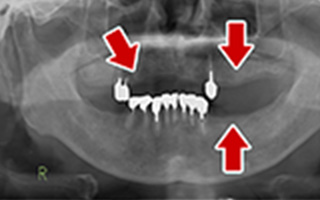

Before

After

| 68歳 男性 | 紹介 |

|---|---|

| 主訴 | れ歯が合わない 食べにくい 人生を豊かにしたい |

| 処置内容 |

上顎4本で12歯(オールオン4)、下顎4本5歯 上下抜歯即時埋入、即時荷重(手術当日にインプラントの上に仮歯装着) |

| 治療費用 | 上顎: 約220万(税込) 下顎: 約180万円(税込) |

| 治療期間 | 上顎: 9ヶ月 下顎: 6ヶ月 |

| リスク |

術後の腫れ、痛み(ピークは3日後、1週間で軽減) 上部構造物、仮歯の破折、人工歯根脱落リスクがあります |